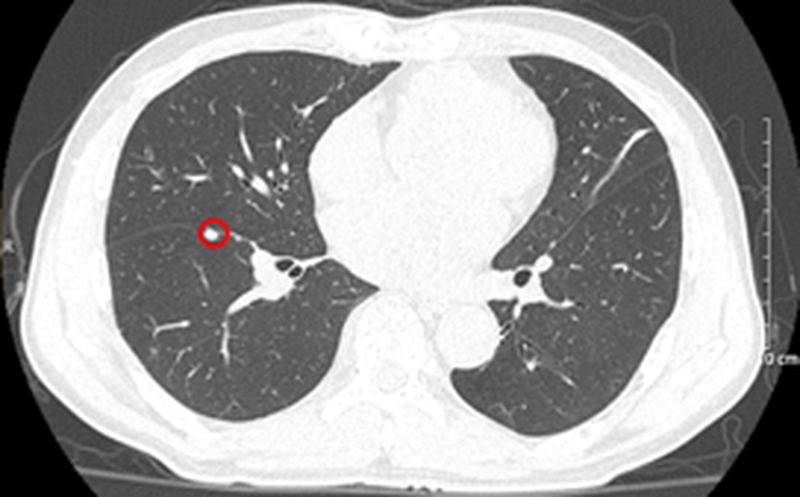

Bệnh nhân khám tại Khoa Khám bệnh, Bệnh viện Bạch Mai, chụp cắt lớp vi tính lồng ngực phát hiện khối, nốt ở nhu mô phổi và khối nhu mô gan. Bệnh nhân sau đó được chuyển đến Trung tâm Y học hạt nhân và Ung bướu.

Nhu mô hạ phân thùy VII có vài khối, nốt kích thước lớn nhất 33x26mm giảm tỷ trọng trước tiêm, ngấm thuốc thì động mạch (vòng tròn đỏ), thải thuốc thì tĩnh mạch cửa (vòng tròn).

Căn cứ vào các kết quả cận lâm sàng, xét nghiệm… bệnh nhân được chẩn đoán xác định ung thư phổi trái không tế bào nhỏ di căn phổi EGFR (+), giai đoạn IV cT3N0M1 – Ung thư đường mật type ống nhỏ di căn hạch rốn gan, giai đoạn IIIB cT2N1M0/viêm gan B.